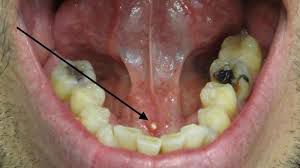

How do you treat salivary stones? Sialolithiasis treatment depends on the size and location of the stone. Treatments may include home remedies, antibiotics, in-office stone removal or, in some cases, surgery. Home remedies Most of the time, salivary gland stones go away on their own with conservative treatment. You might be able to push the stone out of your salivary duct by drinking lots of water, applying heat or massaging the area. You can also try sucking on lemon drops or other sour candy to stimulate saliva production. Antibiotics If you’ve developed an infection as a result of a salivary gland stone, your healthcare provider will probably prescribe antibiotics. You should take these exactly as directed. In-office stone removal If home remedies aren’t successful, your healthcare provider may try to remove the stone by gently probing the area with a blunt instrument. Sialolithiasis surgery Larger salivary gland stones may require surgery. During this procedure, a surgeon inserts an endoscope into your salivary duct to locate the stone. They’ll use a special instrument to remove the stone. In some cases, a small incision is necessary. Salivary gland removal In rare instances, you may need to have your salivary gland surgically removed. Healthcare providers reserve this treatment for people with severe, recurring (returning) symptoms, or if the stone is in a location that isn’t amendable to removal by conservative